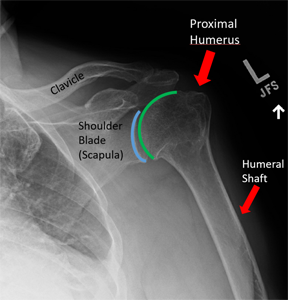

어깨뼈 골절의 입원 기간은 다양하며 상황에 따라 다를 수 있습니다. 일반적으로 어깨 골절의 경우 상완골 골절로 분류되며, 핀고정 수술이 필요한 경우 보통 1주에서 2주 정도의 입원 기간이 필요합니다. 그러나 교통사고나 다른 상황으로 어깨뼈 골절이 더 복잡한 경우에는 입원 기간이 더 길어질 수 있습니다. 따라서 개별 환자의 상태와 치료 방법에 따라 입원 기간이 결정됩니다.

어깨뼈 골절 수술 후, 입원 중에는 주로 진통제가 투여되어 통증을 관리합니다. 이로써 입원 중에는 통증이 그리 심하지 않게 느껴질 수 있습니다. 상완골 골절의 경우 핀고정 수술이 주로 시행되며, 수술 후에는 상완골의 고정이 유지됩니다.